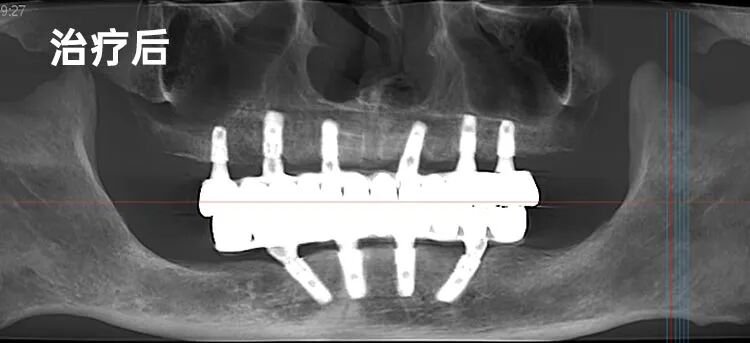

“谭先生,别担心。咱们的方案好比盖一栋特别稳当的房子,虽然地基条件需要处理,但我们有专门的‘加固’技术。”他用盖楼的比喻,将“下颌种植4颗马龙桥修复,上颌6搭6即刻修复”的综合方案娓娓道来,复杂的技术被拆解成听得懂、摸得着的步骤。

手术当日,李院长精湛的技艺与数字化精准操作,让谭先生体验了一场真正意义上的“舒适旅程”。术后,重获新生的喜悦溢于言表。